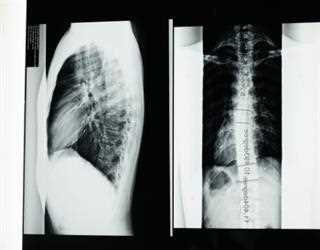

Scoliosis is a sideways curve in your backbone (or spine). Often, it first shows up when you're a child or teenager. The angle of the curve may be small, large

A mild scoliosis curve can go unnoticed to the untrained eye. However, if the curve progresses, various signs and symptoms can become obvious.